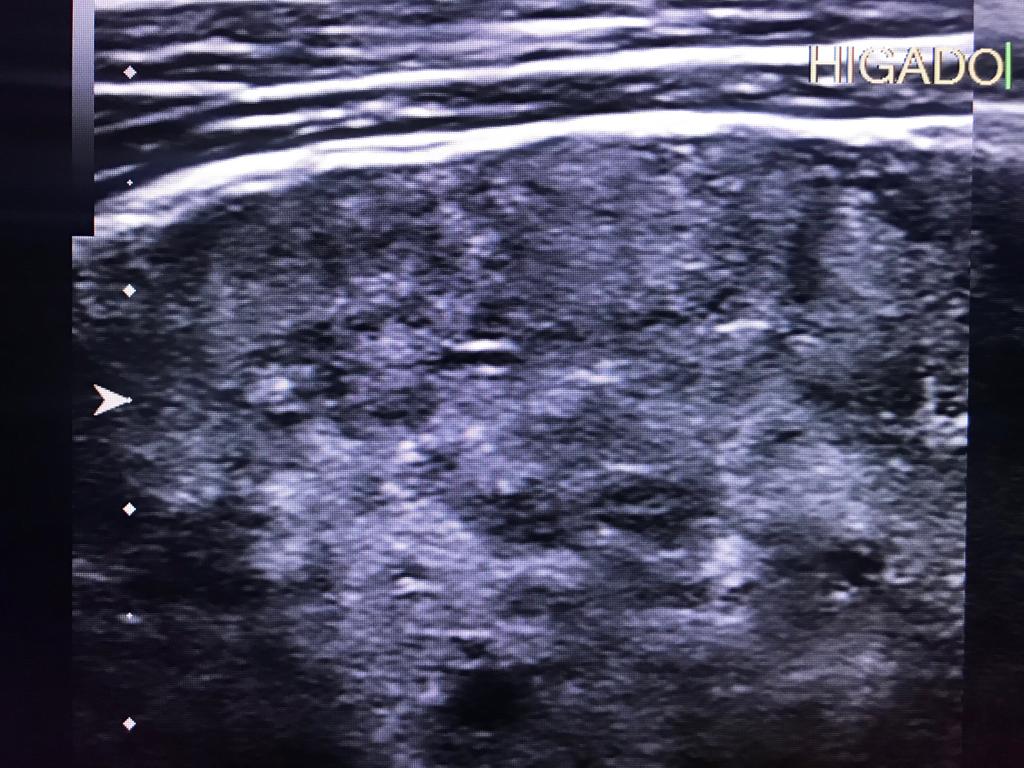

Masculino de 52 años, con cirrosis hepática. La elastografía ecográfica evidencia fibrosis Categoría F3 según escala de METAVIR y la presencia de múltiples nodulaciones, que en su mayoría son menores a 2 cm.

En este contexto, toda nodulación mayor de 1 cm, debe ser evaluada idealmente con RM trifásica con secuencia de Difusión , para discriminar si se trata de nódulos de regeneración , nódulos displásicos o hepatocarcinoma.